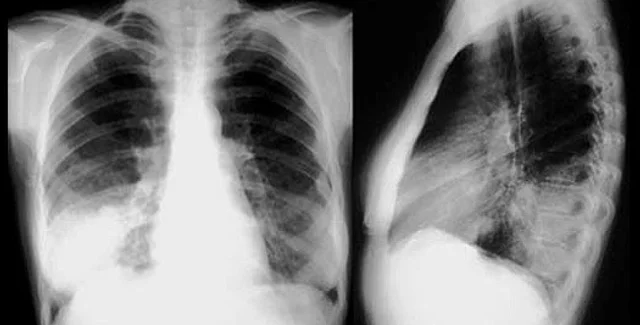

В ДНК рака легких генетики насчитали 23 тысячи ошибок - в значительной степени спровоцированных воздействием табачного дыма. Из этого ученые сделали вывод, что у среднего курильщика на каждые 15 выкуренных сигарет приходится по одному нарушению генетического кода.